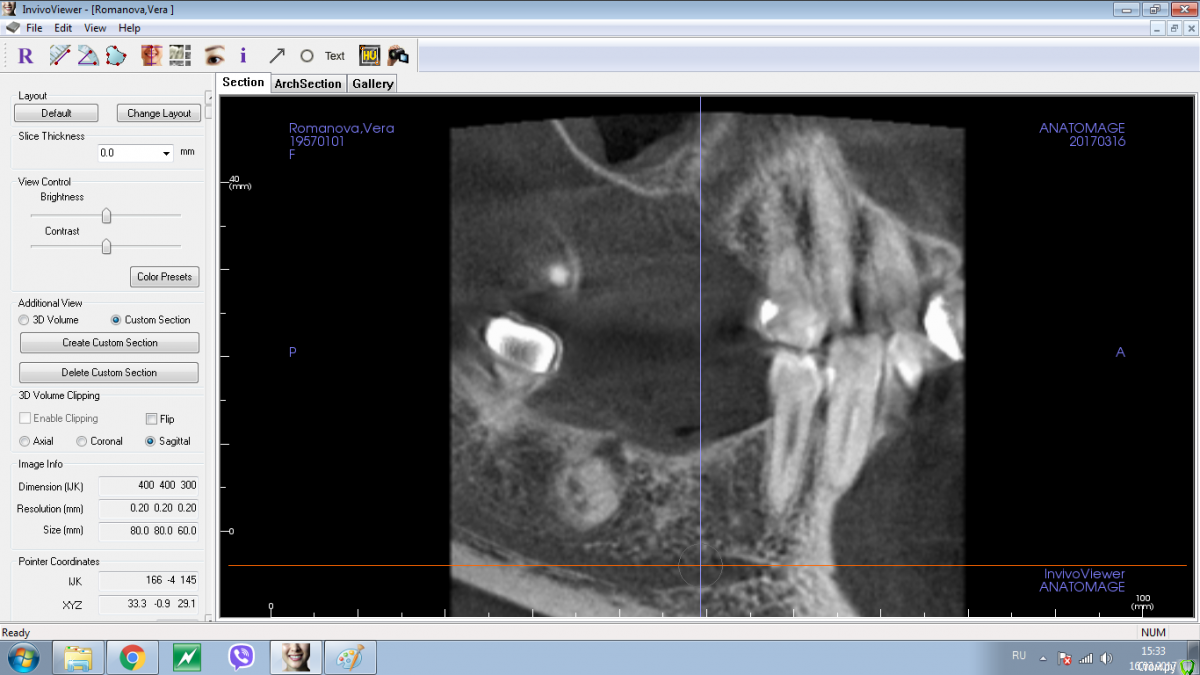

Shakirbura Опубликовано 18 марта, 2017 Поделиться Опубликовано 18 марта, 2017 Здравствуйте, коллеги!Пациентка обратилась по поводу протезирования на имплантатах. На снимке обнаружил вот такое образование. Раньше не встречал. Какими должны быть мои действия в таком случае?Спасибо! Ссылка на комментарий

Andrey Shiryaev Опубликовано 18 марта, 2017 Поделиться Опубликовано 18 марта, 2017 Похоже на остеому. Ссылка на комментарий

BORA Опубликовано 18 марта, 2017 Поделиться Опубликовано 18 марта, 2017 Остатки "красного" зуба Ссылка на комментарий

Kovalov Igor Опубликовано 19 марта, 2017 Поделиться Опубликовано 19 марта, 2017 Конденсирующая остеома.Покажите на Фейсбуке Рогацкину Дмитрию , читал что ставят прям в остеому Ссылка на комментарий

Карен Аванесов Опубликовано 19 марта, 2017 Поделиться Опубликовано 19 марта, 2017 Аккуратно убрать, поставить имплантат, при необходимости графт, если это остатки зуба будет видно. если нло на гистологию. Ссылка на комментарий

Shakirbura Опубликовано 19 марта, 2017 Автор Поделиться Опубликовано 19 марта, 2017 Спасибо! При извлечении этой остеомы могут возникнут какие то сложности? Ссылка на комментарий